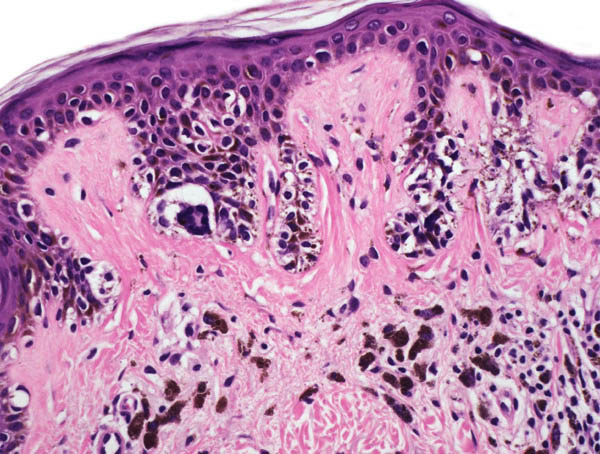

Een

dysplastische naevus is een naevus met histologisch

tekenen van onrust, maar onvoldoende criteria om te kunnen spreken van een

melanoom. Het is een histologische

term (naevus met dysplastische kenmerken). Deze histologische kenmerken zijn:

verlenging van retelijsten, bridging, toename van aantal (gevacuoliseerde) melanocyten,

soms in nestjes op de dermo-epidermale overgang, geen (of nauwelijks) ascentie

in epidermis. Melanocyten soms spoelvormig, groot, pleomorf, en met fijnstoffig

pigment, in ernstiger gevallen onregelmatige opbouw, atypische melanocytaire

hyperplasie (nucleaire atypie, grote, irregulaire polychromatische kernen).

![Histologie van een dysplastische naevus (click on photo to enlarge) [source: www.derm101.com] Histologie van een dysplastische naevus](../../../images/dysplastischenaevus1PA1z.jpg) |

| dysplastische

naevus, bridging |

nestjes,

pigment |

bridging,

nestjes |